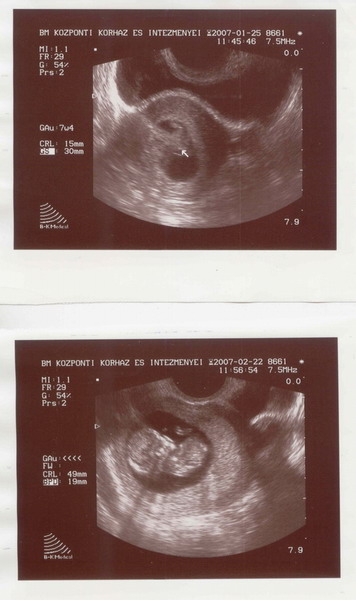

Gratulálok az UH eredményhez.És ha benneteket megnyugtat a Down-szűrés,csak csináltassátok meg.